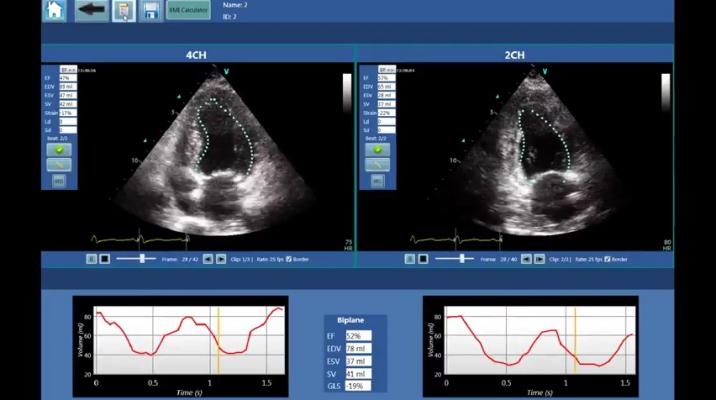

LVivo EF analysis software. Image courtesy of DiA Imaging Analysis

DiA has marketed its automated imaging analysis technology to deliver immediate, accurate and reproducible imaging interpretation of ultrasound for point-of-care settings. These tools utilize advanced, proprietary pattern recognition and sophisticated machine learning algorithms that can dramatically improve monitoring of patient conditions, offering physicians powerful tools to support their decisions.

The company's U.S. Food and Drug Administration (FDA)- and CE-cleared cognitive image processing tools are based on advanced pattern recognition and machine learning algorithms that automatically imitate the way the human eye identifies borders and motion, producing accurate and reliable data for the use of physicians.